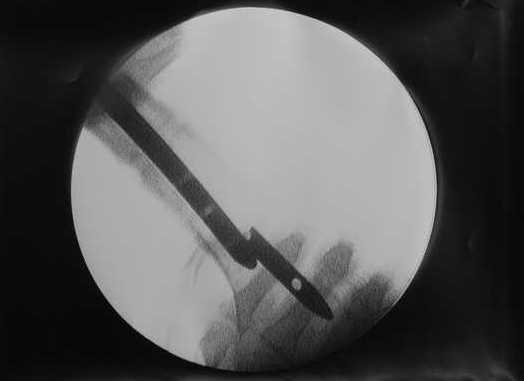

Пациенту М., 30-ти лет, 1,5 года назад в одной из московских больниц был выполнен остеосинтез бедренной кости штифтом UFN (диаметр штифта 9 мм).

К нам больной поступил с признаками ложного сустава бедренной кости, перелома

штифта и дистального блокирующего винта (images 1,2,3).

27 марта выполнено удаление блокирующих винтов (сломанный винт пришлось высверливать цапфен-бором), сломанного штифта (дистальный фрагмент удален через канал, образованный разверткой из коленного сустава - image 4),

рассверливание костно-мозгового канала, реостеосинтез штифтом UFN (при проведении штифта в дистальном отломке мы использовали поляризующий винт, диаметр штифта 10 мм). После операции в связи гемартрозом дважды (на 1 и 3 сутки) выполняли пункцию коленного сустава. Сейчас признаков скопления жидкости в полости сустава нет. Послеоперационные рентгенограммы - images 5, 6, 7.